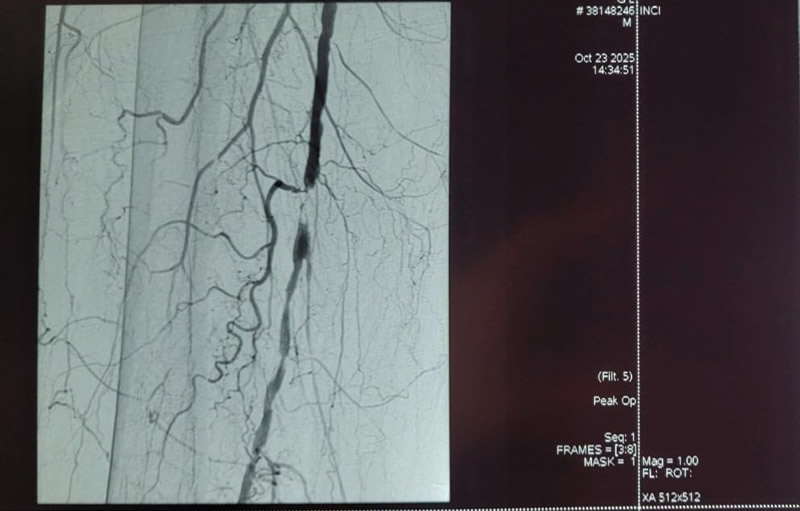

El jueves 23 de octubre, el equipo del Servicio de Cirugía Vascular del HCFFAA, bajo la dirección del Jefe del Servicio Cap. (M) Martín Álvez da Cruz, realizó por primera vez un tratamiento de revascularización de miembros inferiores utilizando litotricia intravascular (Shockwave®).

El procedimiento se llevó a cabo en un paciente de 77 años, con múltiples antecedentes y amputación del miembro inferior izquierdo, logrando en el miembro inferior derecho la desobstrucción arterial y la restauración del flujo sanguíneo hacia el pie.

El dispositivo de última generación utilizado para el procedimiento, permite tratar la obstrucción arterial periférica provocando la fractura de la placa de calcio en la pared arterial, lo cual permite recuperar la luz del vaso y aumentar la permeabilidad de la angioplastia con balón.